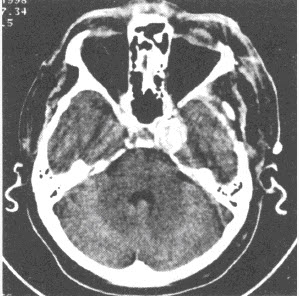

2、单项选择题 患者,女,80岁,被人发现昏迷,大小便失禁10小时入院。体格检查:血压180/100mmHg,心率约110次/分,有房颤,体温37℃,浅昏迷,右侧肢体未见自主活动,肌力增高,Babinski征阳性,GCS=E2+V1+M3=6分,有风湿性心脏病和房颤病史,既往超声检查有二尖瓣赘生物。

患者检查图像如下,你考虑何种疾病()

1、多项选择题 患者,女,80岁,被人发现昏迷,大小便失禁10小时入院。体格检查:血压180/100mmHg,心率约110次/分,有房颤,体温37℃,浅昏迷,右侧肢体未见自主活动,肌力增高,Babinski征阳性,GCS=E2+V1+M3=6分,有风湿性心脏病和房颤病史,既往超声检查有二尖瓣赘生物。 你的诊断依据是哪些()

A.昏迷伴大小便失禁10小时

B.CT示脑实质内大面积均匀低密度区

C.脑实质内见类圆形密度增高影,边缘见大面积低密度区

D.脑内占位性病变,瘤周水肿明显

E.脑沟、脑池增宽,密度与脑脊液密度相似

F.CT示脑实质内低密度区不强化